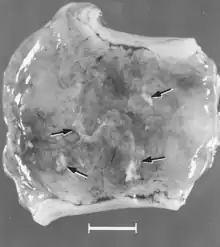

Macroscopic changes of embryos are death followed by resorption of fluids (Fig. 4) and then soft tissues (Fig. 5). Virus and viral antigen are widely distributed in tissues of infected embryos and their placentas,[84] and it is probable that microscopic lesions of necrosis and vascular damage, subsequently described for fetuses, also develop in advanced embryos.

Figure 4. Embryos from a gilt experimentally infected oronasally immediately after breeding and killed 22 days later. Bar = 1 cm. (Top) Noninfected, clinically normal embryo (arrow) and associated extraembryonic membranes; (bottom) PPV-infected, dead littermate embryo (arrow) and associated extraembryonic membranes, recent death, no obvious resorption of soft tissues.[84]

Figure 5. Segment of uterus opened to show necrotic remnants of a partially resorbed PPV-infected embryo (arrows) and associated extraembryonic membranes of a gilt experimentally infected oronasally immediately after breeding and killed 22 days later; remnants are laden with virus and viral antigen. Bar = 1 cm.[84]